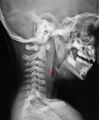

الحيز البلعومي الخلفي (retropharyngeal space، اختصاراً "RPS"[1][2])، هو حيز كامن[2][3] وتجويف عميق مستقل في الرأس والرقبة[1] يقع خلف البلعوم.[4] The RPS is bounded anteriorly by the buccopharyngeal fascia, posteriorly by the alar fascia, and laterally by the carotid sheath. It extends between the base of the skull superiorly, and the mediastinum inferiorly.[1] It contains the retropharyngeal lymph nodes.[2] Its function is to facilitate movements in the superoinferior axis of the larynx, pharynx, and esophagus in relation to the cervical spine.[3]

If more than half of the size of the C2 vertebra, it may indicate retropharyngeal abscess.[7]